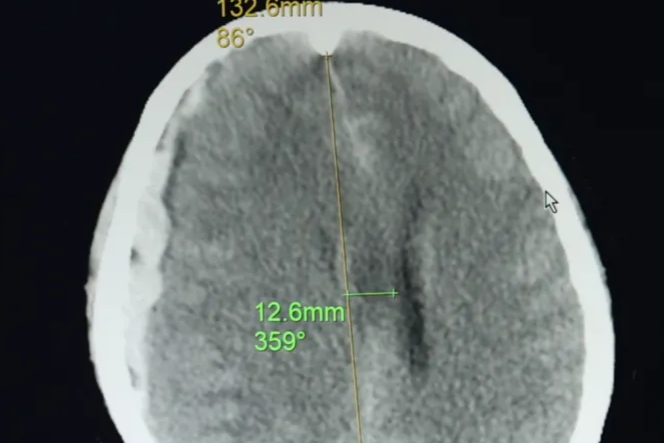

摔一跤后,头盖骨「消失」三个月是什么体验?